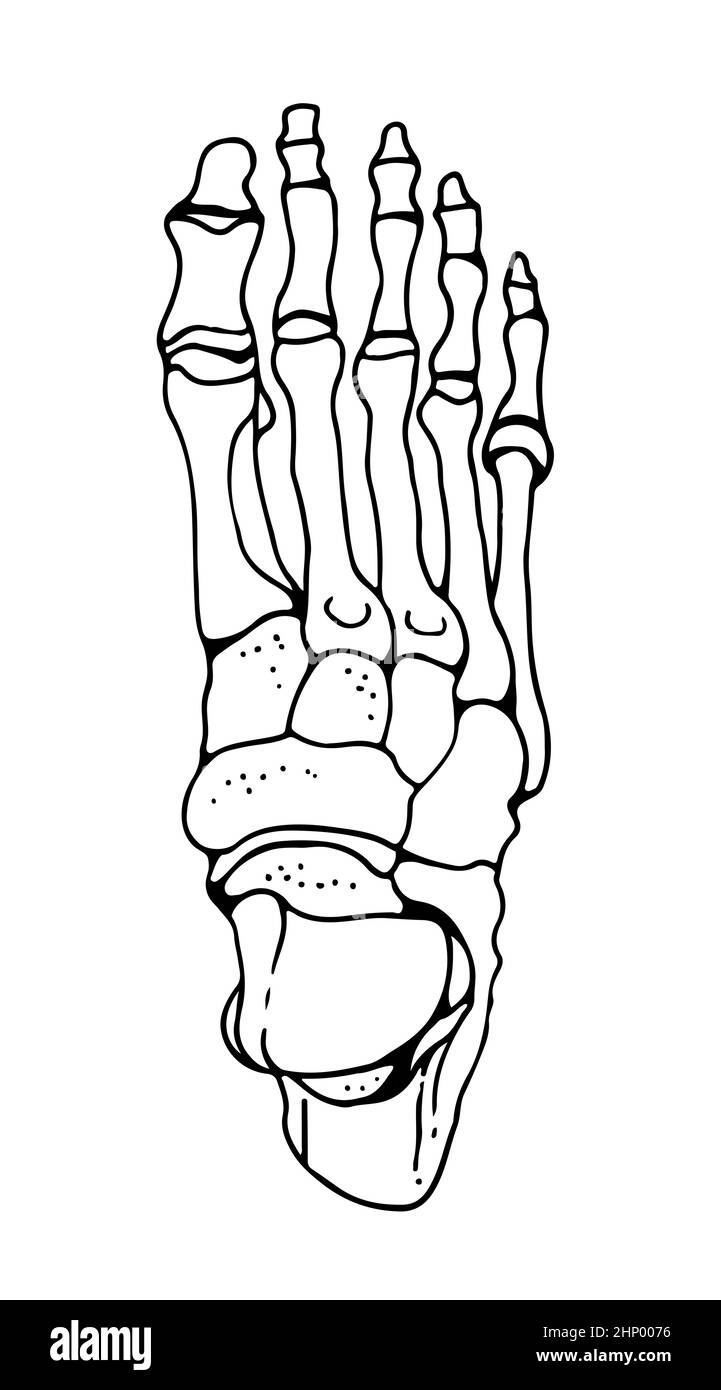

RF2HP0076–OS du pied humain, illustration vectorielle dessinée à la main isolée sur fond blanc, esquisse anatomique en médecine orthopédique

RF2WNN754–Illustration médicale des principales parties des os du pied en vue antérieure, avec annotations.

RF2EFH4NT–Affiche prête pour la salle de classe montrant les os du pied dans des vues anatomiques et éclatées.

RF2HJXCXK–Anatomie du pied.OS et fascia Plantar.Illustration vectorielle réaliste. Vue de dessous et vue latérale